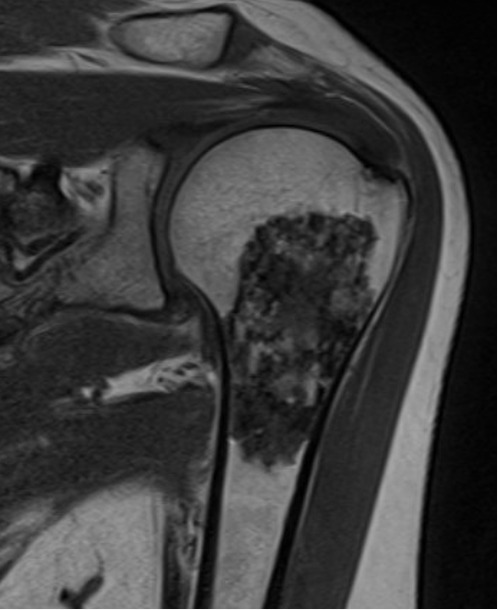

Condrossarcoma: É um tumor maligno primário que forma cartilagem. Acomete principalmente os adultos, nos ossos da bacia, fêmur e úmero.

A avaliação de um médico especializado é fundamental para um diagnóstico correto. Devido a sua raridade e poucos sintomas, o diagnóstico é difícil e pode ser retardado. O exame físico minucioso e a avaliação da história clínica são importantes para a diferenciação de tumores para outras doenças mais comuns, como abscessos, infecções, doenças inflamatórias e vasculares. A Ressonância Magnética é o melhor exame para investigação de tumores de partes moles, proporcionando uma boa percepção da anatomia local e características do tumor. A biópsia através de agulha ou por meio de incisão pode ser indicada para auxiliar o diagnóstico e guiar o tratamento definitivo.